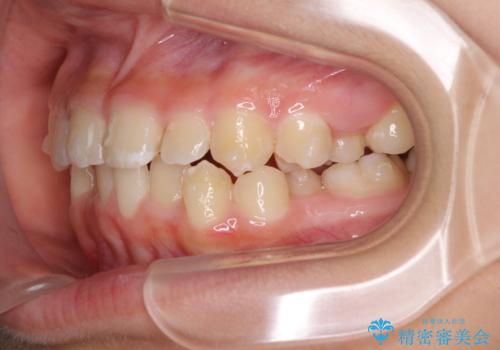

遠方から新幹線で通院 急速拡大装置とインビザラインによる矯正治療

- 小児矯正の頃から診察を行っている患者様です。

上顎骨の幅が下顎骨よりも小さいので、拡大装置により骨幅を広げて上下関係を改善し、その後インビザラインにて歯並びを整えることとしました。

上下の骨幅を改善したことで、スムーズに歯列矯正を行うことができました。

インビザライン治療開始直後に遠方に引っ越しをされたため、通院間隔が長くなり、治療期間が長くなりましたが、しっかりと治療を行うことができました。